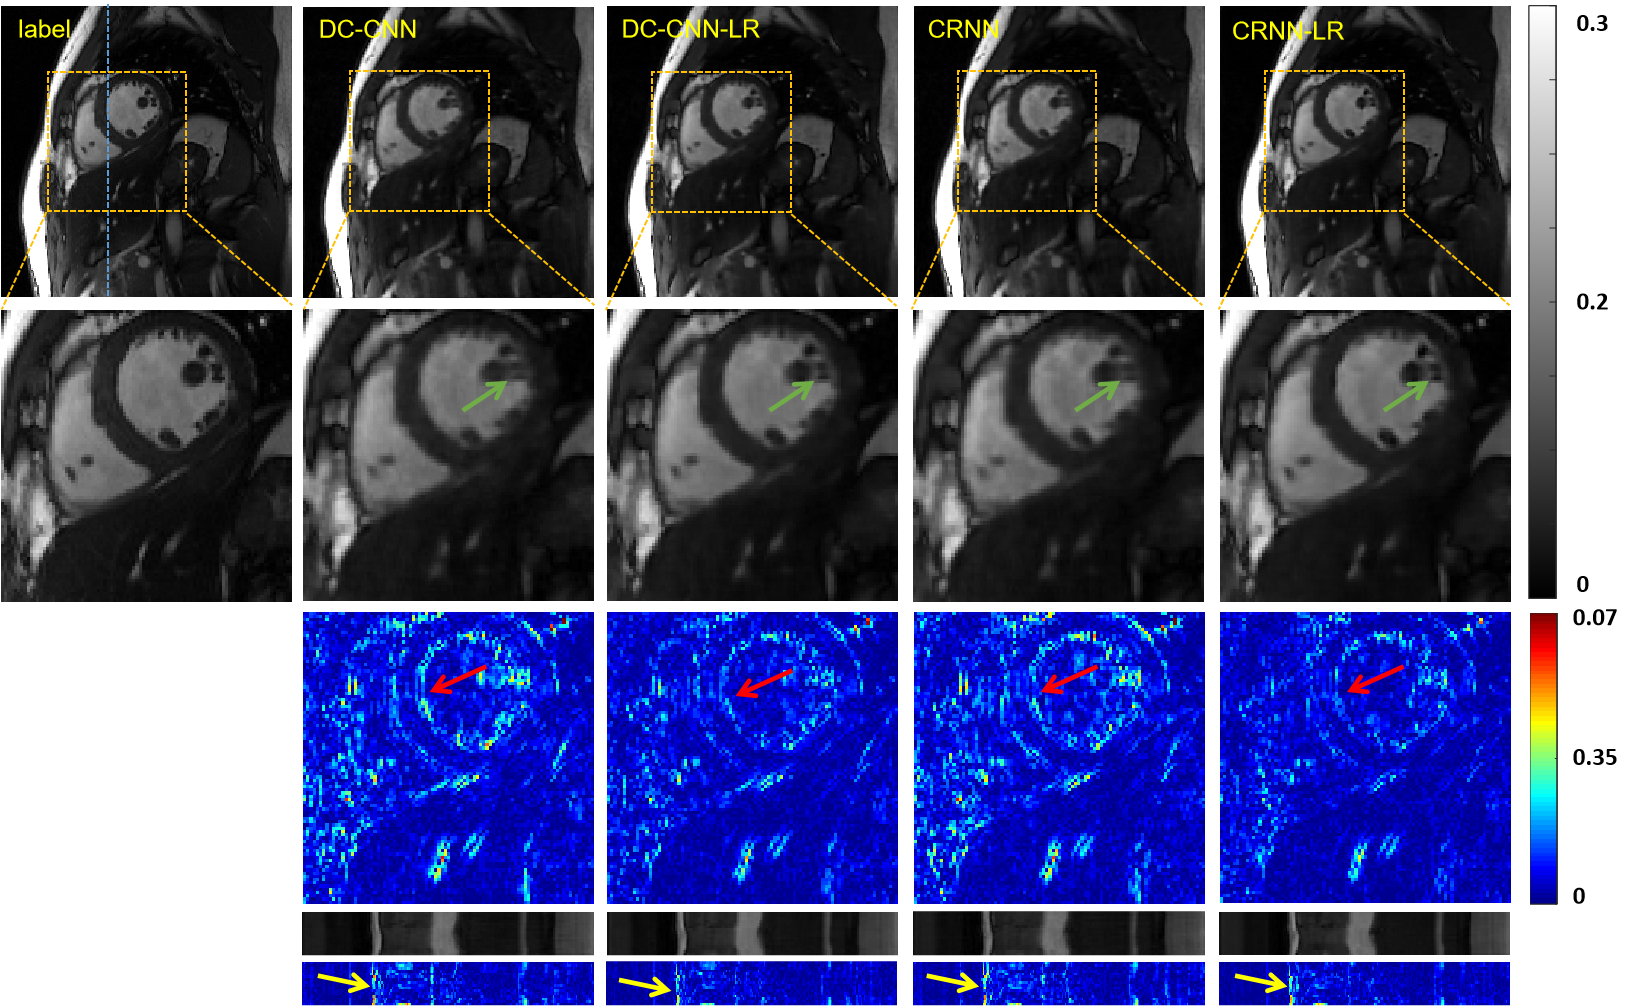

III-C The Reconstruction Performance of the Proposed Plug-and-play LR Module

To demonstrate the efficacy of the proposed plug-and-play LR module, we embedded it in the state-of-the-art CNN-based DC-CNN [10] and CRNN [11] methods at location numbered 2 (L2), where we can obtain optimal performance as we explored in the following Section IV.A.

The reconstruction results of CNN-LR at 8-fold acceleration are shown in Fig.5. It is obvious to observe that by embedding LR module, the reconstruction results exhibit more details (as shown in the green arrow) and the smoothness is eliminated. The quantitative evaluations were also provided in Table II. All three performance metrics were significantly improved (DC-CNN: 2.0e-5 lower in MSE, 1.4dB higher in PSNR and 0.009 higher in SSIM. CRNN: 2.7e-5 lower in MSE, 2.1dB higher in PSNR and 0.01 higher in SSIM). Both qualitatively and quantitatively, the second scheme of deep low-rank prior achieves superior reconstruction performance.

DC-CNN and CRNN have consistent conclusions: The embedding of the LR module can effectively improve the reconstruction results. This lightweight LR module enables the neural networks to quickly access low-rank prior of dynamic data. It is also very easy to embed in other dynamically correlated deep learning models because it does not require changes to the topology of the network.